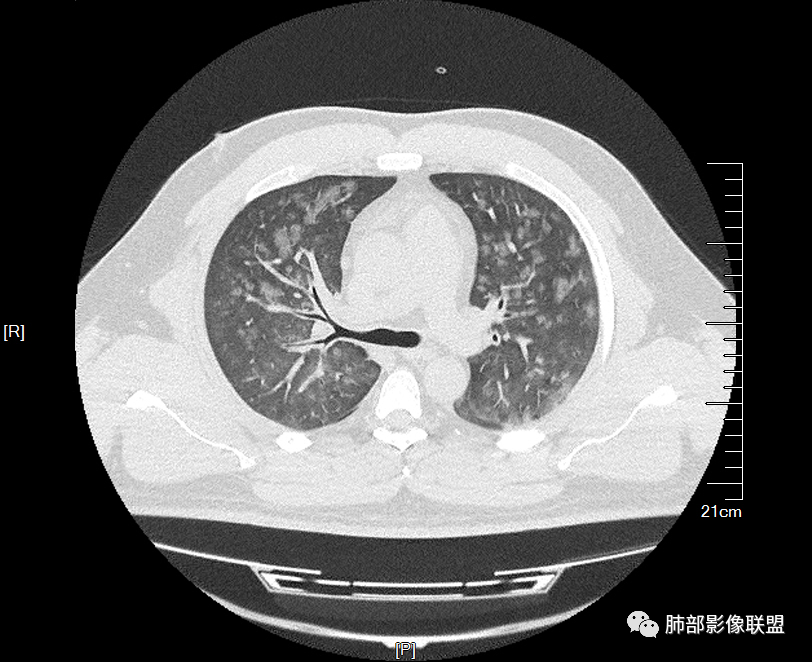

双肺多发弥漫性磨玻璃结节影,大小不一,形态不规则,部分融合,支气管未见明显扩张,部分血管束略增粗,叶裂胸膜增厚,临床有痛风,左足痛6天,考虑:1:痛风结节(一般实性结节,很少磨玻璃结节影)2:血管炎?3:病毒性肺炎(水痘-疱疹肺炎?)

双肺多发腺泡结节及磨玻璃,小叶间隔增厚(大网格状),腺泡结节内及磨玻璃内可见细网格影(小叶内间隔增厚),影像表现符合肺泡出血改变,血肌酐升高,考虑肺肾综合征。鉴别肺水肿。

两肺弥漫向心分布的腺泡结节,部分融合,两肺小叶间隔增厚,血肌肝高,考虑肺泡性肺水肿

年轻男性,痛风史,高血压史,肌酐高,左足痛6天入院。胸CT:双肺多发弥漫性磨玻璃结节影,大小不一,部分融合,上中下肺都有,中内带多,胸膜下少。部分血管束略增粗,小叶内间隔、小叶间隔增厚,下肺明显,左室大。叶裂胸膜增厚。临床有痛风,左足痛6天,考虑:心衰、间质性肺水肿?弥漫性肺泡出血?鉴别:MPA,肺肾综合征,痛风结节等。

青年男性,有肾功能不全史和痛风史,这个影像分布有个典型的特点,全部是以中央间质周围的渗出性改变,这个改变主要就是两种可能,一种是肾功能不全导致的血管通透性增高导致的肾性肺水肿,一种是出血导致的DAH改变,具体是哪种,影像上不好简单的鉴别,需要结合更多临床资料综合分析。

多发GGO结节,边界清,以全小叶、小叶中心为主:

小叶间隔增厚,无明显重力趋势

少量积液,脂肪肝

这里有一点重力趋势

中轴间质稍增厚

细网格也明显

中轴间质增厚,小叶间隔增厚,小叶内间质增厚,部分重力作用,双侧对称,胸水,按理淋巴道回流受阻有

肺水肿类病变有

问题是腺泡结节如何解释?